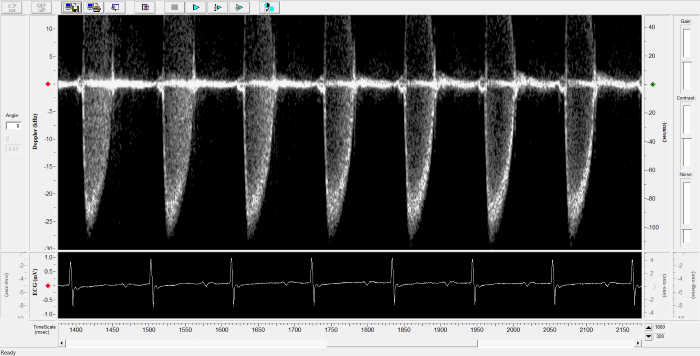

Imaging gallery - Doppler Flow Velocity System

Mouse - Coronary Flow Reserve Imaging. Image Credit: Scintica Instrumentation Inc.

Mouse - Left Anterior Descending Coronary Artery. Image Credit: Scintica Instrumentation Inc.